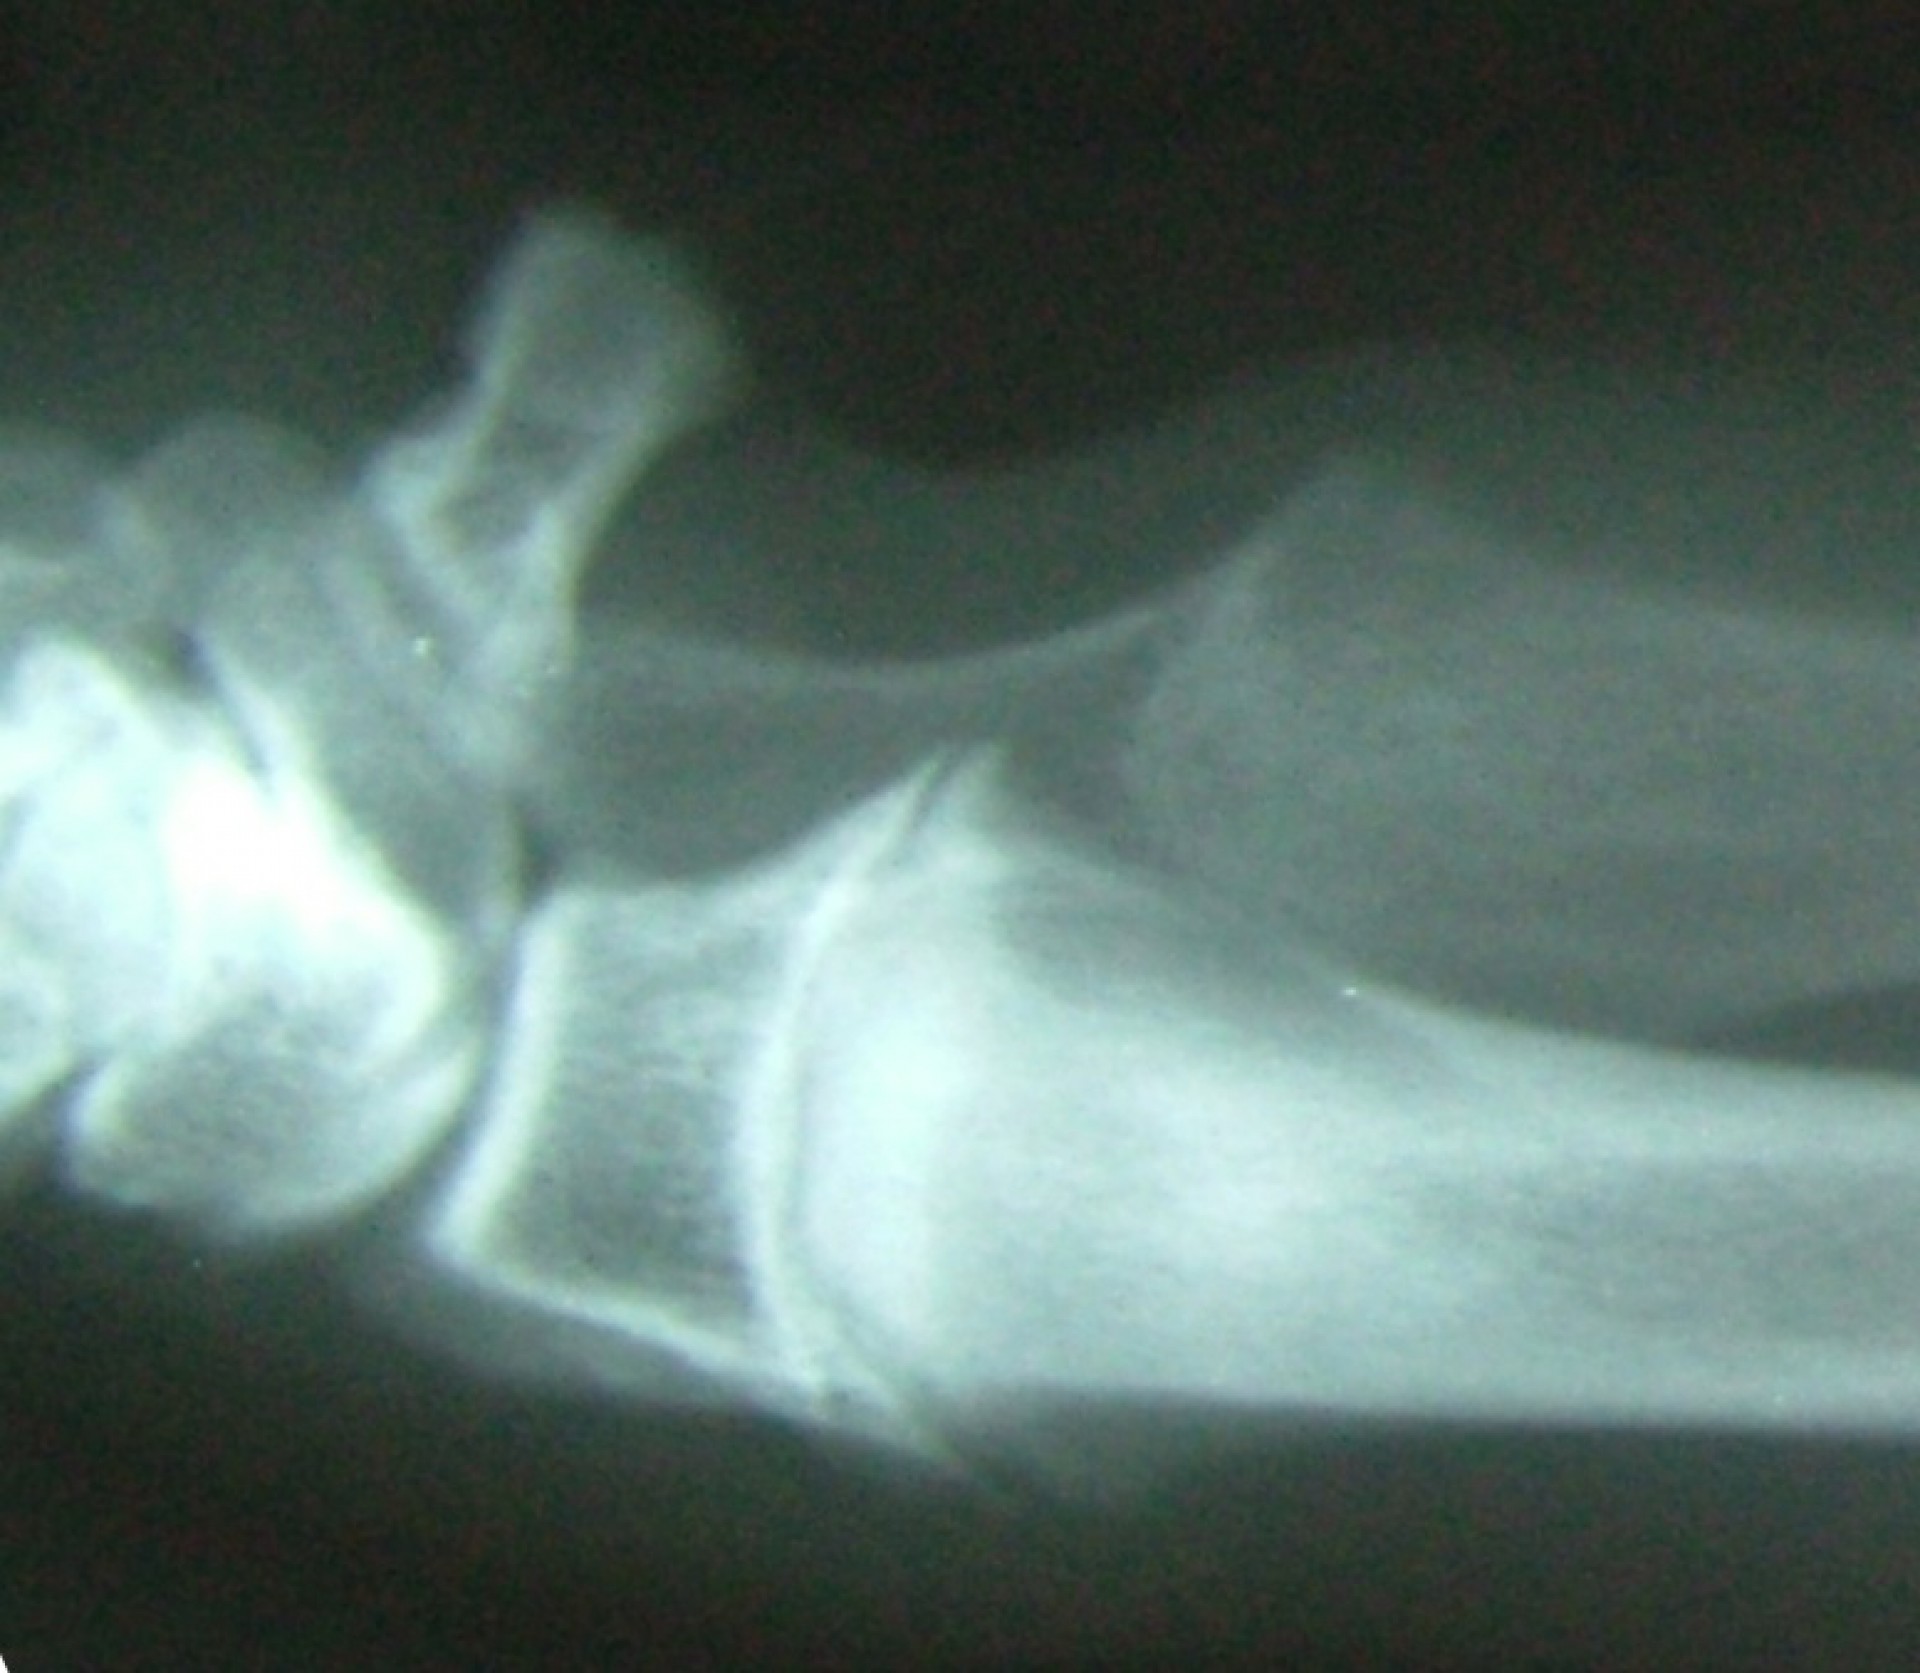

Az alkarcsont növekedési zónájának záródása általában a könyökízületben un.: inkongruenciát okoz. A könyökízület működéséhez az azt alkotó 3 csont (karcsont, könyökcsont, alkarcsont) tökéletes illeszkedése elengedhetetlen. Azokban az esetekben amikor bármely 2, a könyökízület alkotásában résztvevő csont ízületi felszíne nem illeszkedik tökéletesen,rendellenes ízületi alakulásról, inkongruenciáról beszélünk. Ezekben az esetekben az ízületi felszínek nem megfelelő terhelődése azok kopásához, idült ízületgyulladáshoz, következményesen fájdalomhoz vezet.

Az alkarcsont alsó vagy felső növekedési zónájának lezáródása esetén a könyökízületben kialakuló inkongruencia az ízület mozgásának fájdalmasságához, a mozgáspálya beszűküléséhez vezet. Paradox módon az ilyen elváltozás esetén is (mivel az alkarcsont a teherviselő csont) a könyökcsont osteotomiájával, annak növekedésének korlátozásával gyógyítjuk a beteget.

Az idejében észrevett elváltozás esetén, - amennyiben a csövescsontok növekedése még nem állt le -, az ízület normalizálódik, az eredeti funkció visszaáll.Súlyos fokú inkongruencia kialakulása esetén az ízületi funkció már nem állítható vissza. Azokban az esetekben, amikor a súlyos ízületi elváltozás fájdalommal jár az ízület bemerevítésével (arthrodesis) a fájdalom megszüntethető.